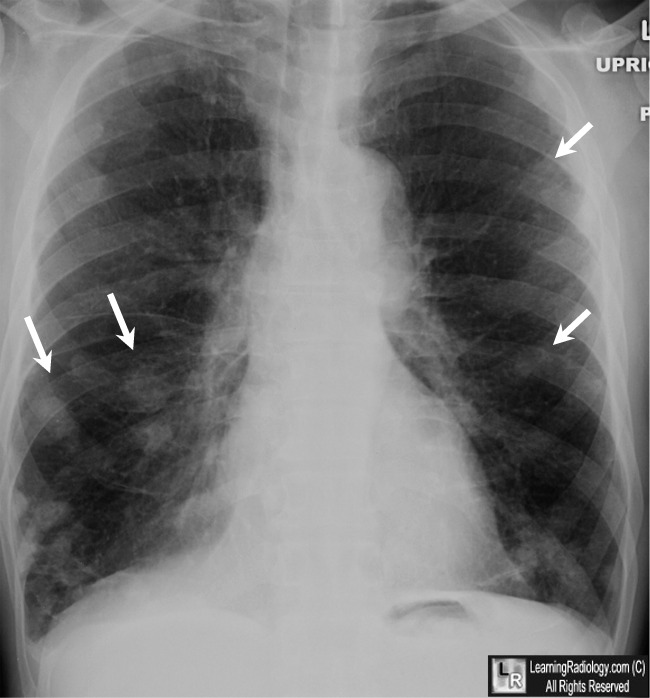

From www.learningradiology.com

LearningRadiology Why Do I Need A Chest X Ray For Rheumatoid Arthritis contact your doctor promptly if you have rheumatoid arthritis and experience any unexplained breathing. radiologists interpreting the chest radiographs of rheumatoid arthritis (ra) patients should report abnormalities. costochondritis is not arthritis in the ribs or the chest and isn't directly related to ra, but inflammation from ra can. learn what types of imaging scans are most. Why Do I Need A Chest X Ray For Rheumatoid Arthritis.